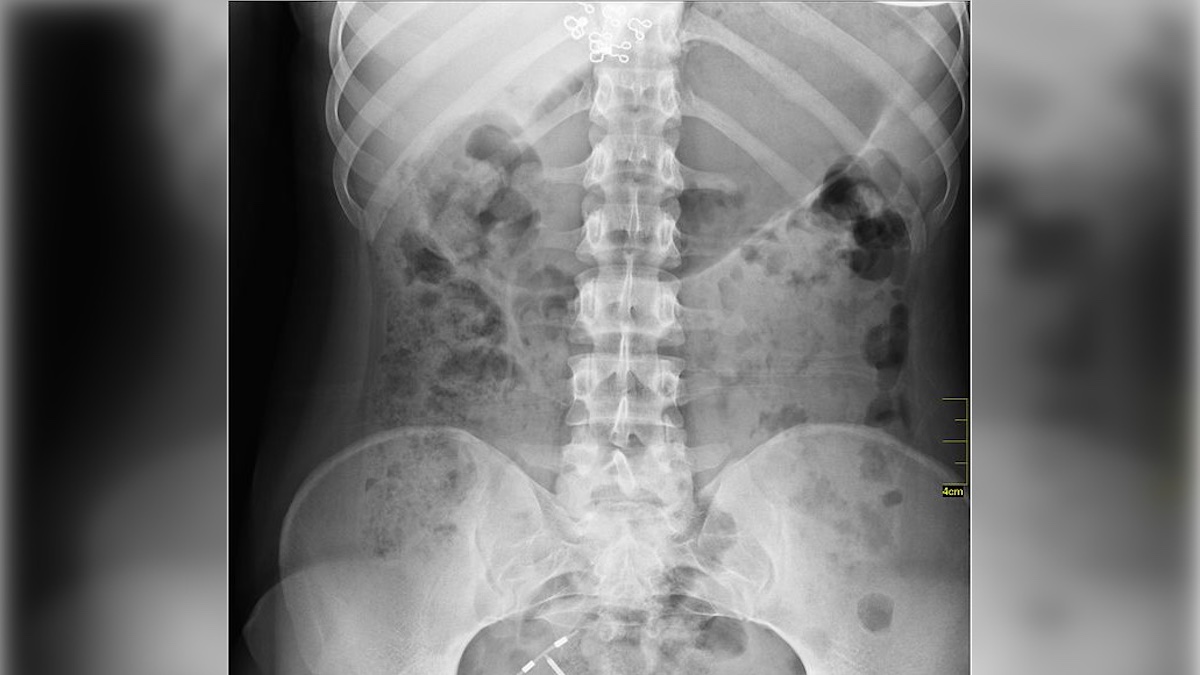

X-Ray by way of Wiki Commons, Nevit Dilmen